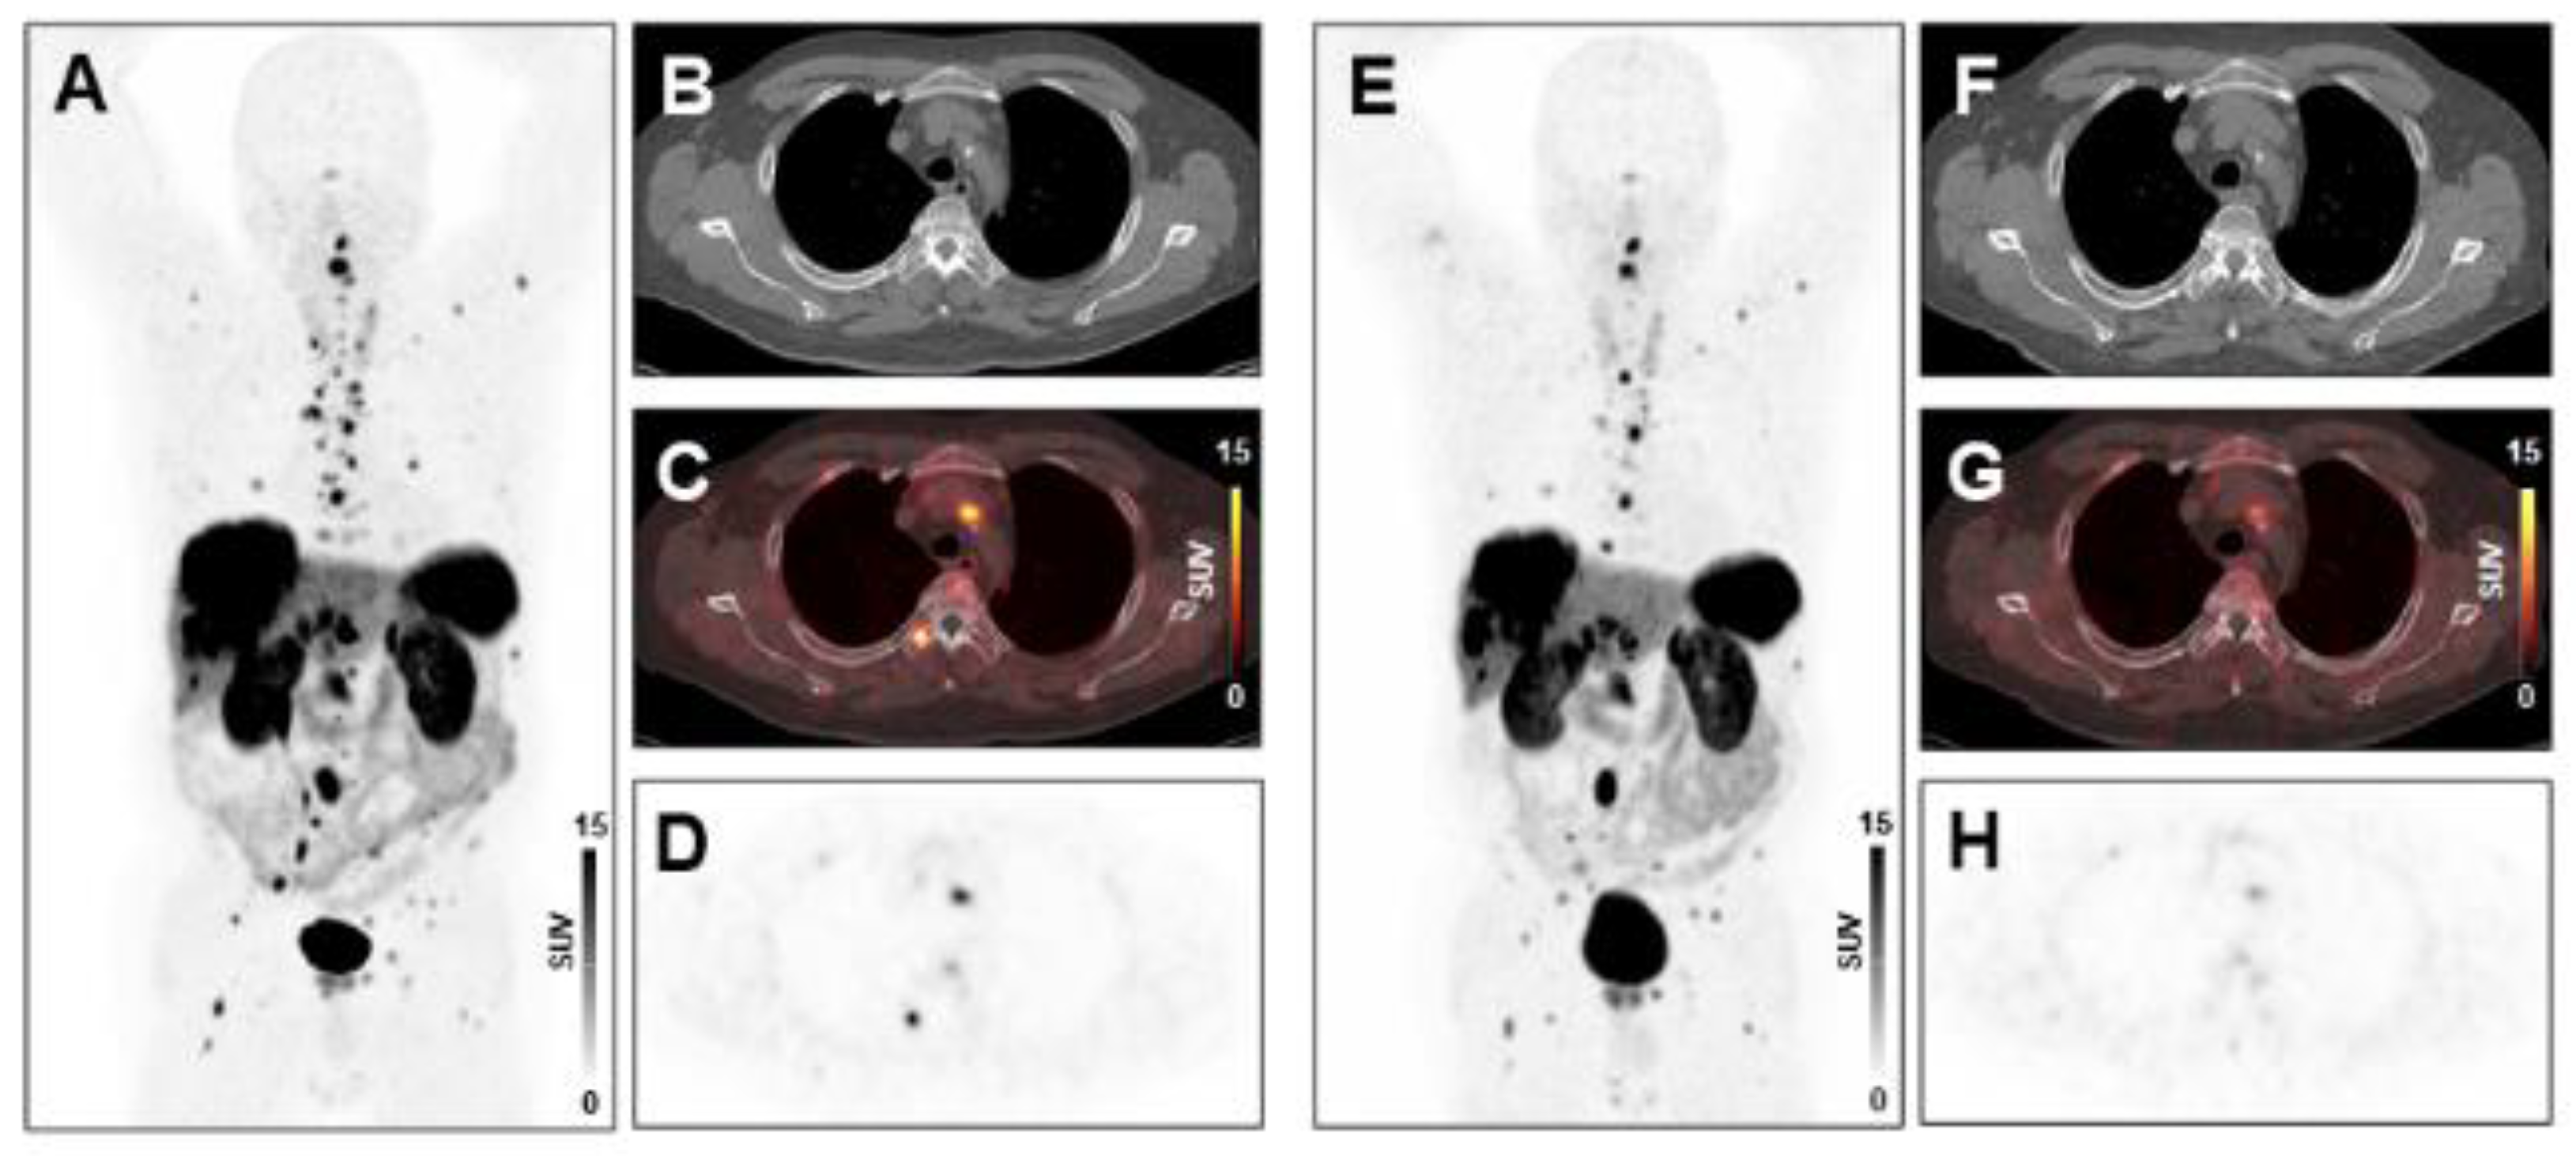

2.3. PET/CT Image Analysis

3.2. Baseline Markers of Systemic Inflammation Are Elevated in Non-Responders to PRRT

3.3. Early Change in Tumor Burden Is Associated with Markers of Systemic Inflammation